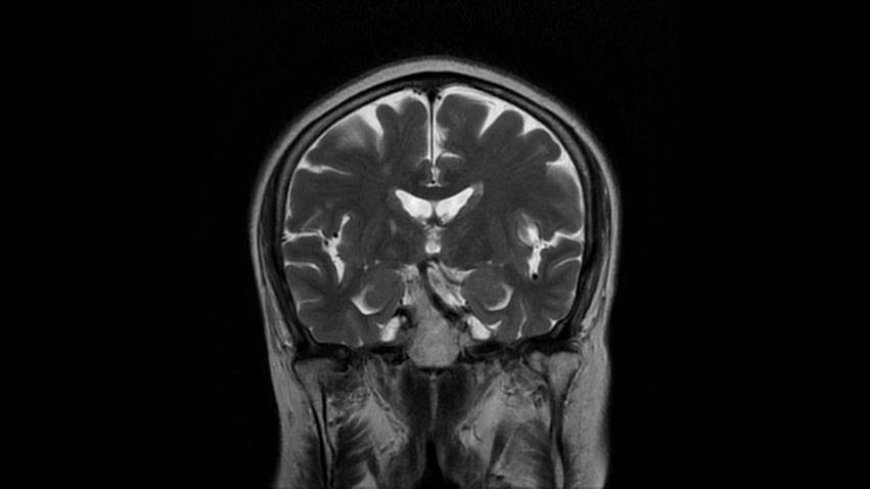

MRI of Brain

Coronal T2